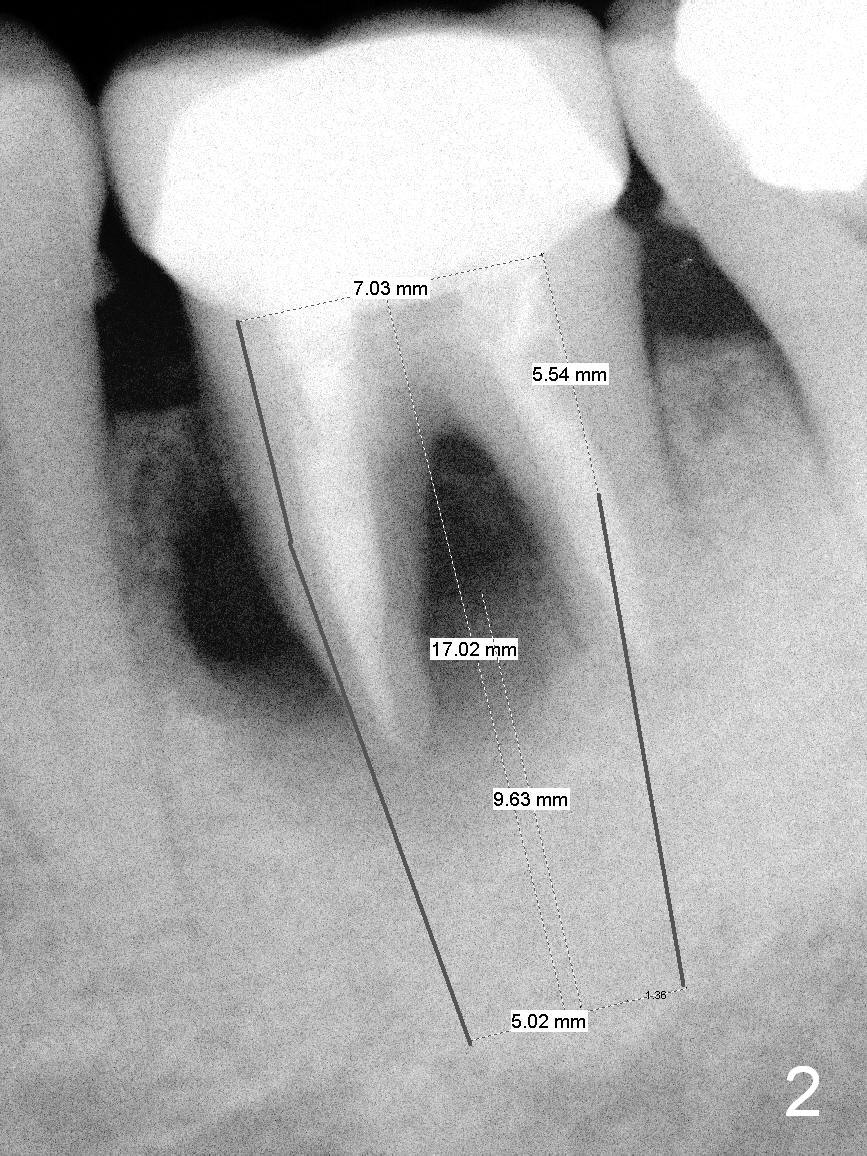

The tooth #19 of a 54-year-old man (FJ) looked normal 2.5 years ago (Fig.1). The patient returns because of 3 fistulae developing around the mesial root of the tooth. Recent PA shows a large radiaolucent defect (Fig.2,3). To place an implant in the middle of the edentulous space, initial osteotomy should be distal because of the large mesial defect.